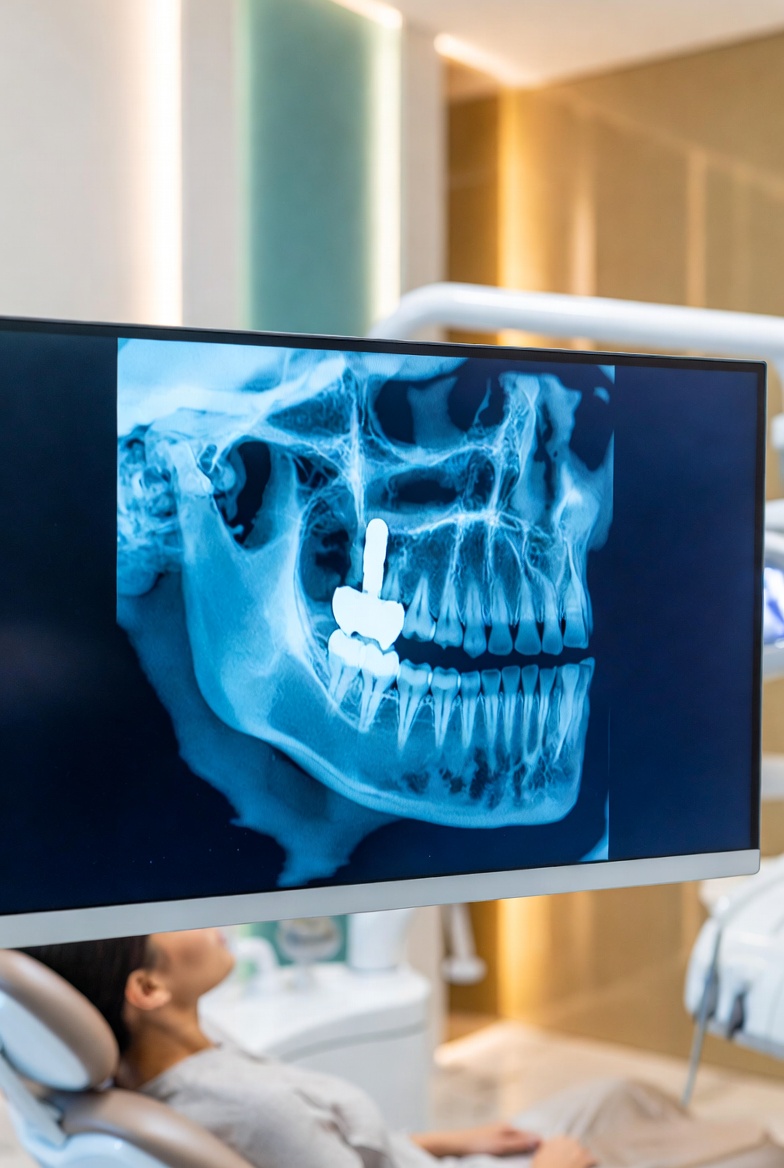

- Greater accuracy: CBCT 3D scans reveal nerve canals and bone density invisible on 2D images.

- Faster treatment planning:your dentist plans implants, extractions, and root canals with precision.

On arrival, your dentist selects the appropriate imaging type based on your clinical needs. A digital dental X-ray Business Bay Dubai takes seconds — sensors are positioned in your mouth and an image appears on screen immediately. For a CBCT cone beam scan Dubai, you stand or sit in the scanner while it rotates once around your head in under 20 seconds. Your dentist reviews all images with you during the same appointment and explains every finding.

A CBCT scan reveals bone density, nerve locations, and 3D tooth structure — essential for implant planning, wisdom teeth, and complex endodontic cases.